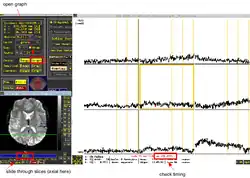

You can also use the graph display in the afni viewer to check slicetiming. When the timing (indx, value, at...) jumps back and forth sliding through the slices in the image depicting the plane in which they were acquired, the slices are acquired interleaved. There should be no more change in timing after slice time correction and when walking through the timeseries in the graph itself the time should increase with TR from volume to volume. Look into the tutorial mentioned in the AFNI Software section of this book for a more detailed description.